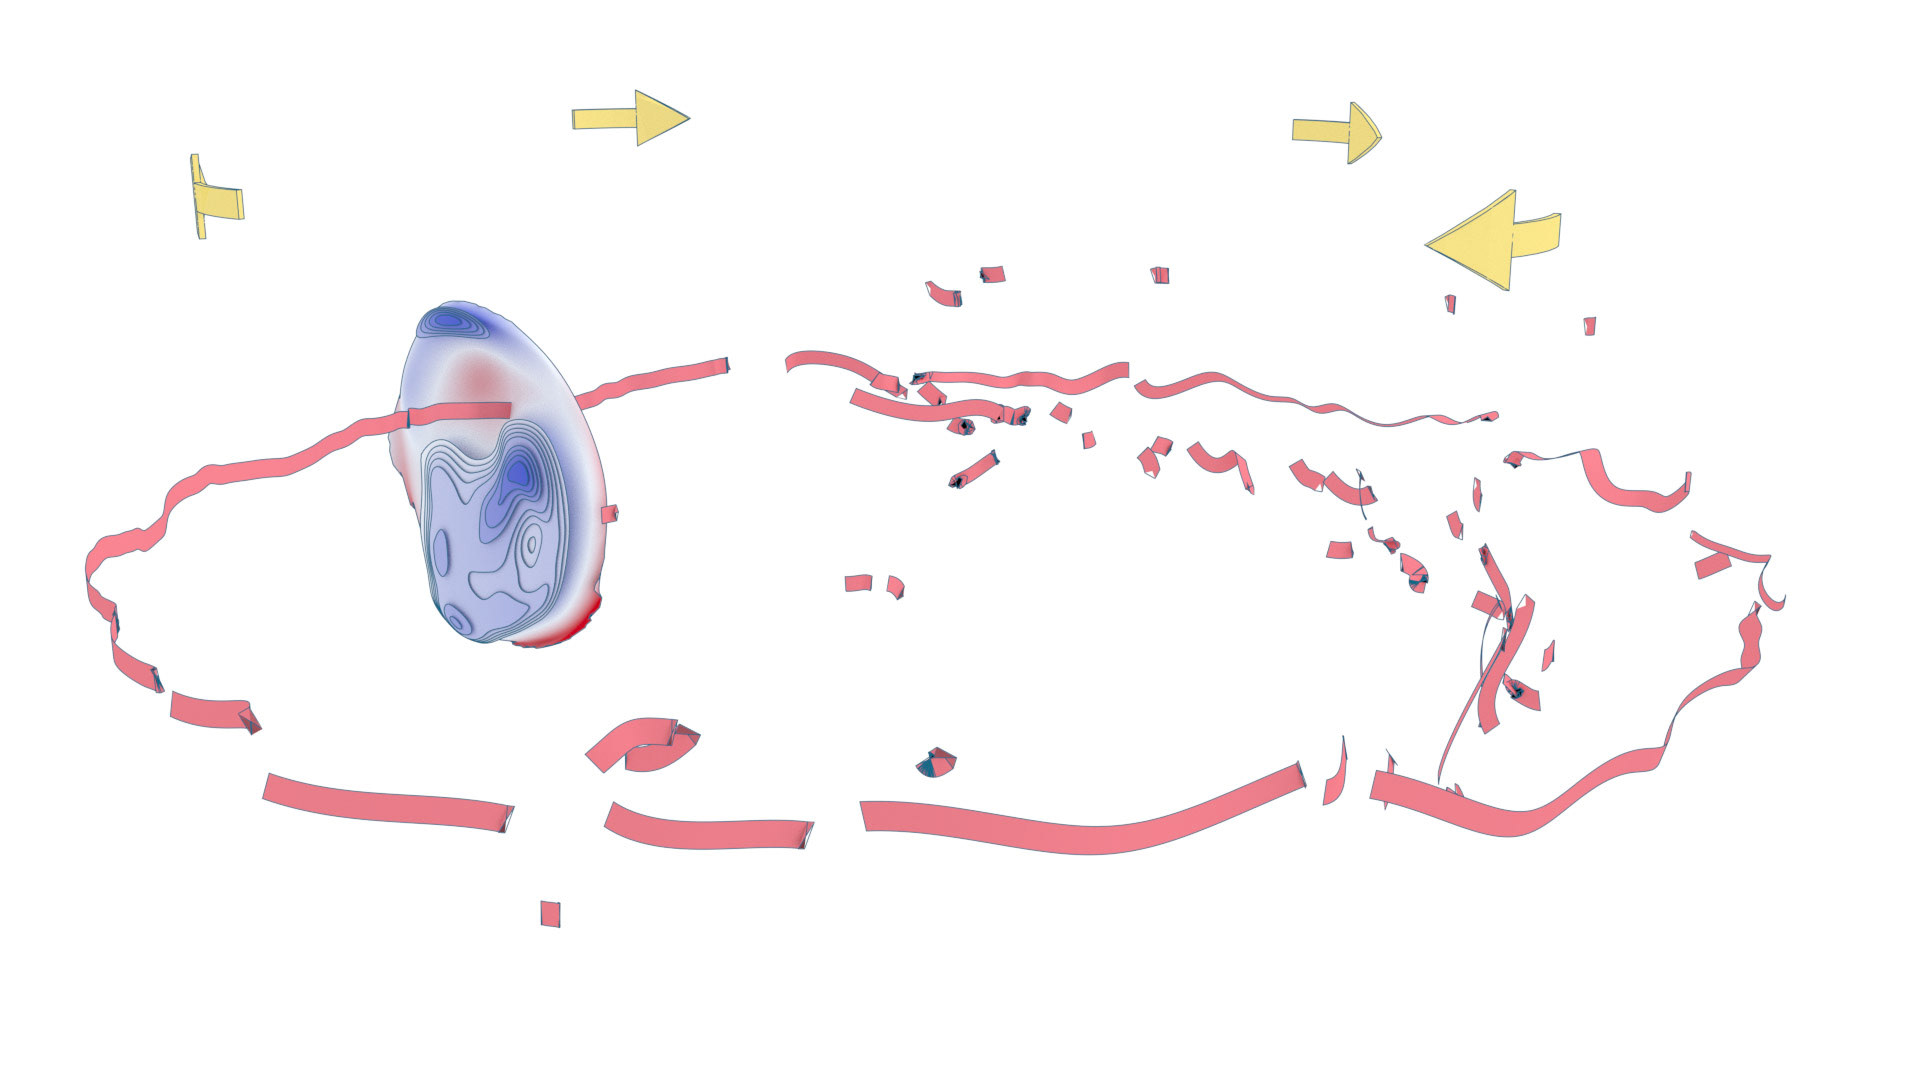

An ongoing collaboration with the Biomedical Simulation Lab (BSL), University of Toronto. In my role, I develop concept sketches and renderings that are then implemented algorithmically. The overall approach is to show turbulent flow visualizations without animation my mapping the transitions among states to carousel that corresponds to the cardiac cycle.